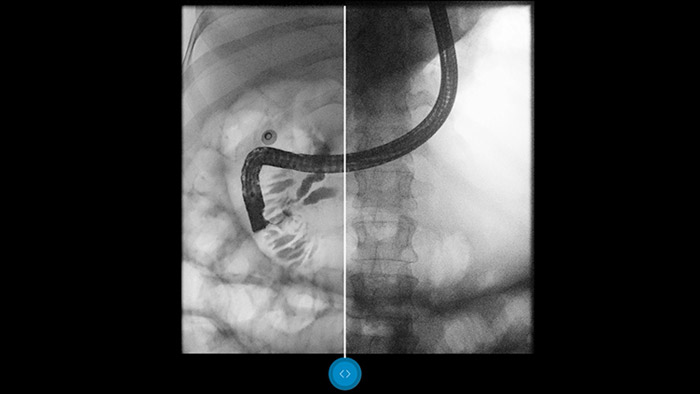

Representación de alta calidad de los detalles de diagnóstico en una fluoroscopia de dosis baja.

Dynamic UNIQUE ofrece una excelente visibilidad de los detalles con supresión del ruido en tiempo real, desde el primer fotograma hasta el último. La información de diagnóstico para cada fotograma se muestra con gran claridad, con el brillo correcto y con una latencia muy baja. La representación de la imagen es coherente y estable, incluso cuando el contenido de la imagen varía rápidamente.

El software de procesamiento de imágenes Dynamic UNIQUE equilibra el contraste. Además, realza los detalles más débiles y brinda una calidad de imagen uniforme, lo cual permite distinguir claramente los huesos de los tejidos blandos.

Compárelo con un procesador de imágenes convencional para ver los beneficios usted mismo.